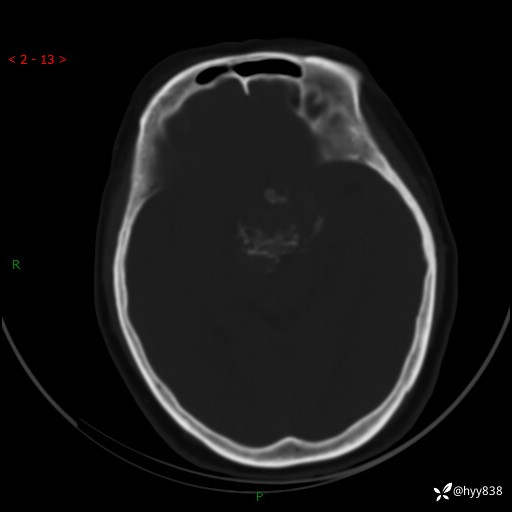

颅脑CT平扫